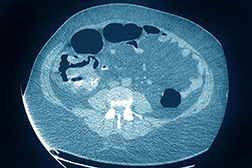

In a colonoscopy, a long, flexible tube with a tiny video camera is threaded through the rectum into the intestine to look for possible cancerous changes. Doctors sometimes remove polyps and other abnormal tissue using the tube during the procedure. Before the pandemic, more than 15 million colonoscopies were performed each year in the US, according to the University of Pennsylvania Abramson Cancer Center.